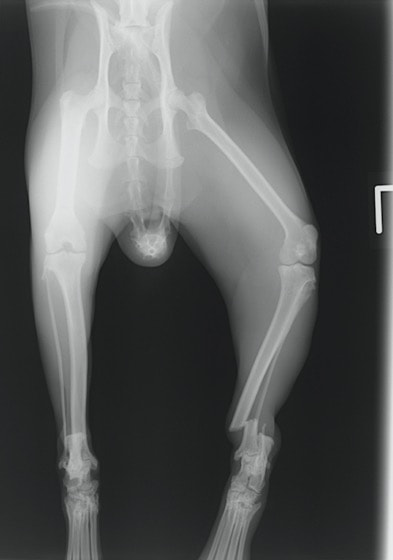

ペルシャ猫 11ヶ月齢 雄

他院にて左大腿骨遠位の成長板骨折(salter-harrisⅠ型)が認められており、治療相談を目的として来院。当院にて、キルシュナーワイヤーを用いたピンニングにより骨折部位の整復を行いました。術後の経過は良好で、現在も経過観察中です。

術前レントゲン

術後レントゲン